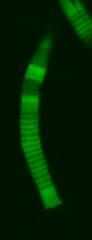

This image shows a breaking rod series.

(Photo Credit: Haeri et al.)